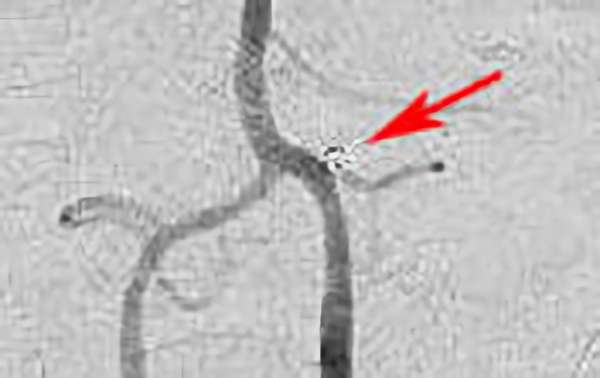

No.1631 手術前